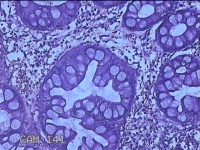

乙状结肠粘膜

性别

男

年龄

52岁

临床诊断

结肠息肉

一般病史

乙状结肠可见息肉

标本名称

大体所见

灰白粉红色组织小米大一团。

图2

自动采图系统很方便,图片采太多没病变的图,几张就够了,而且制片技术急需改进,

有点增生性息肉的感觉